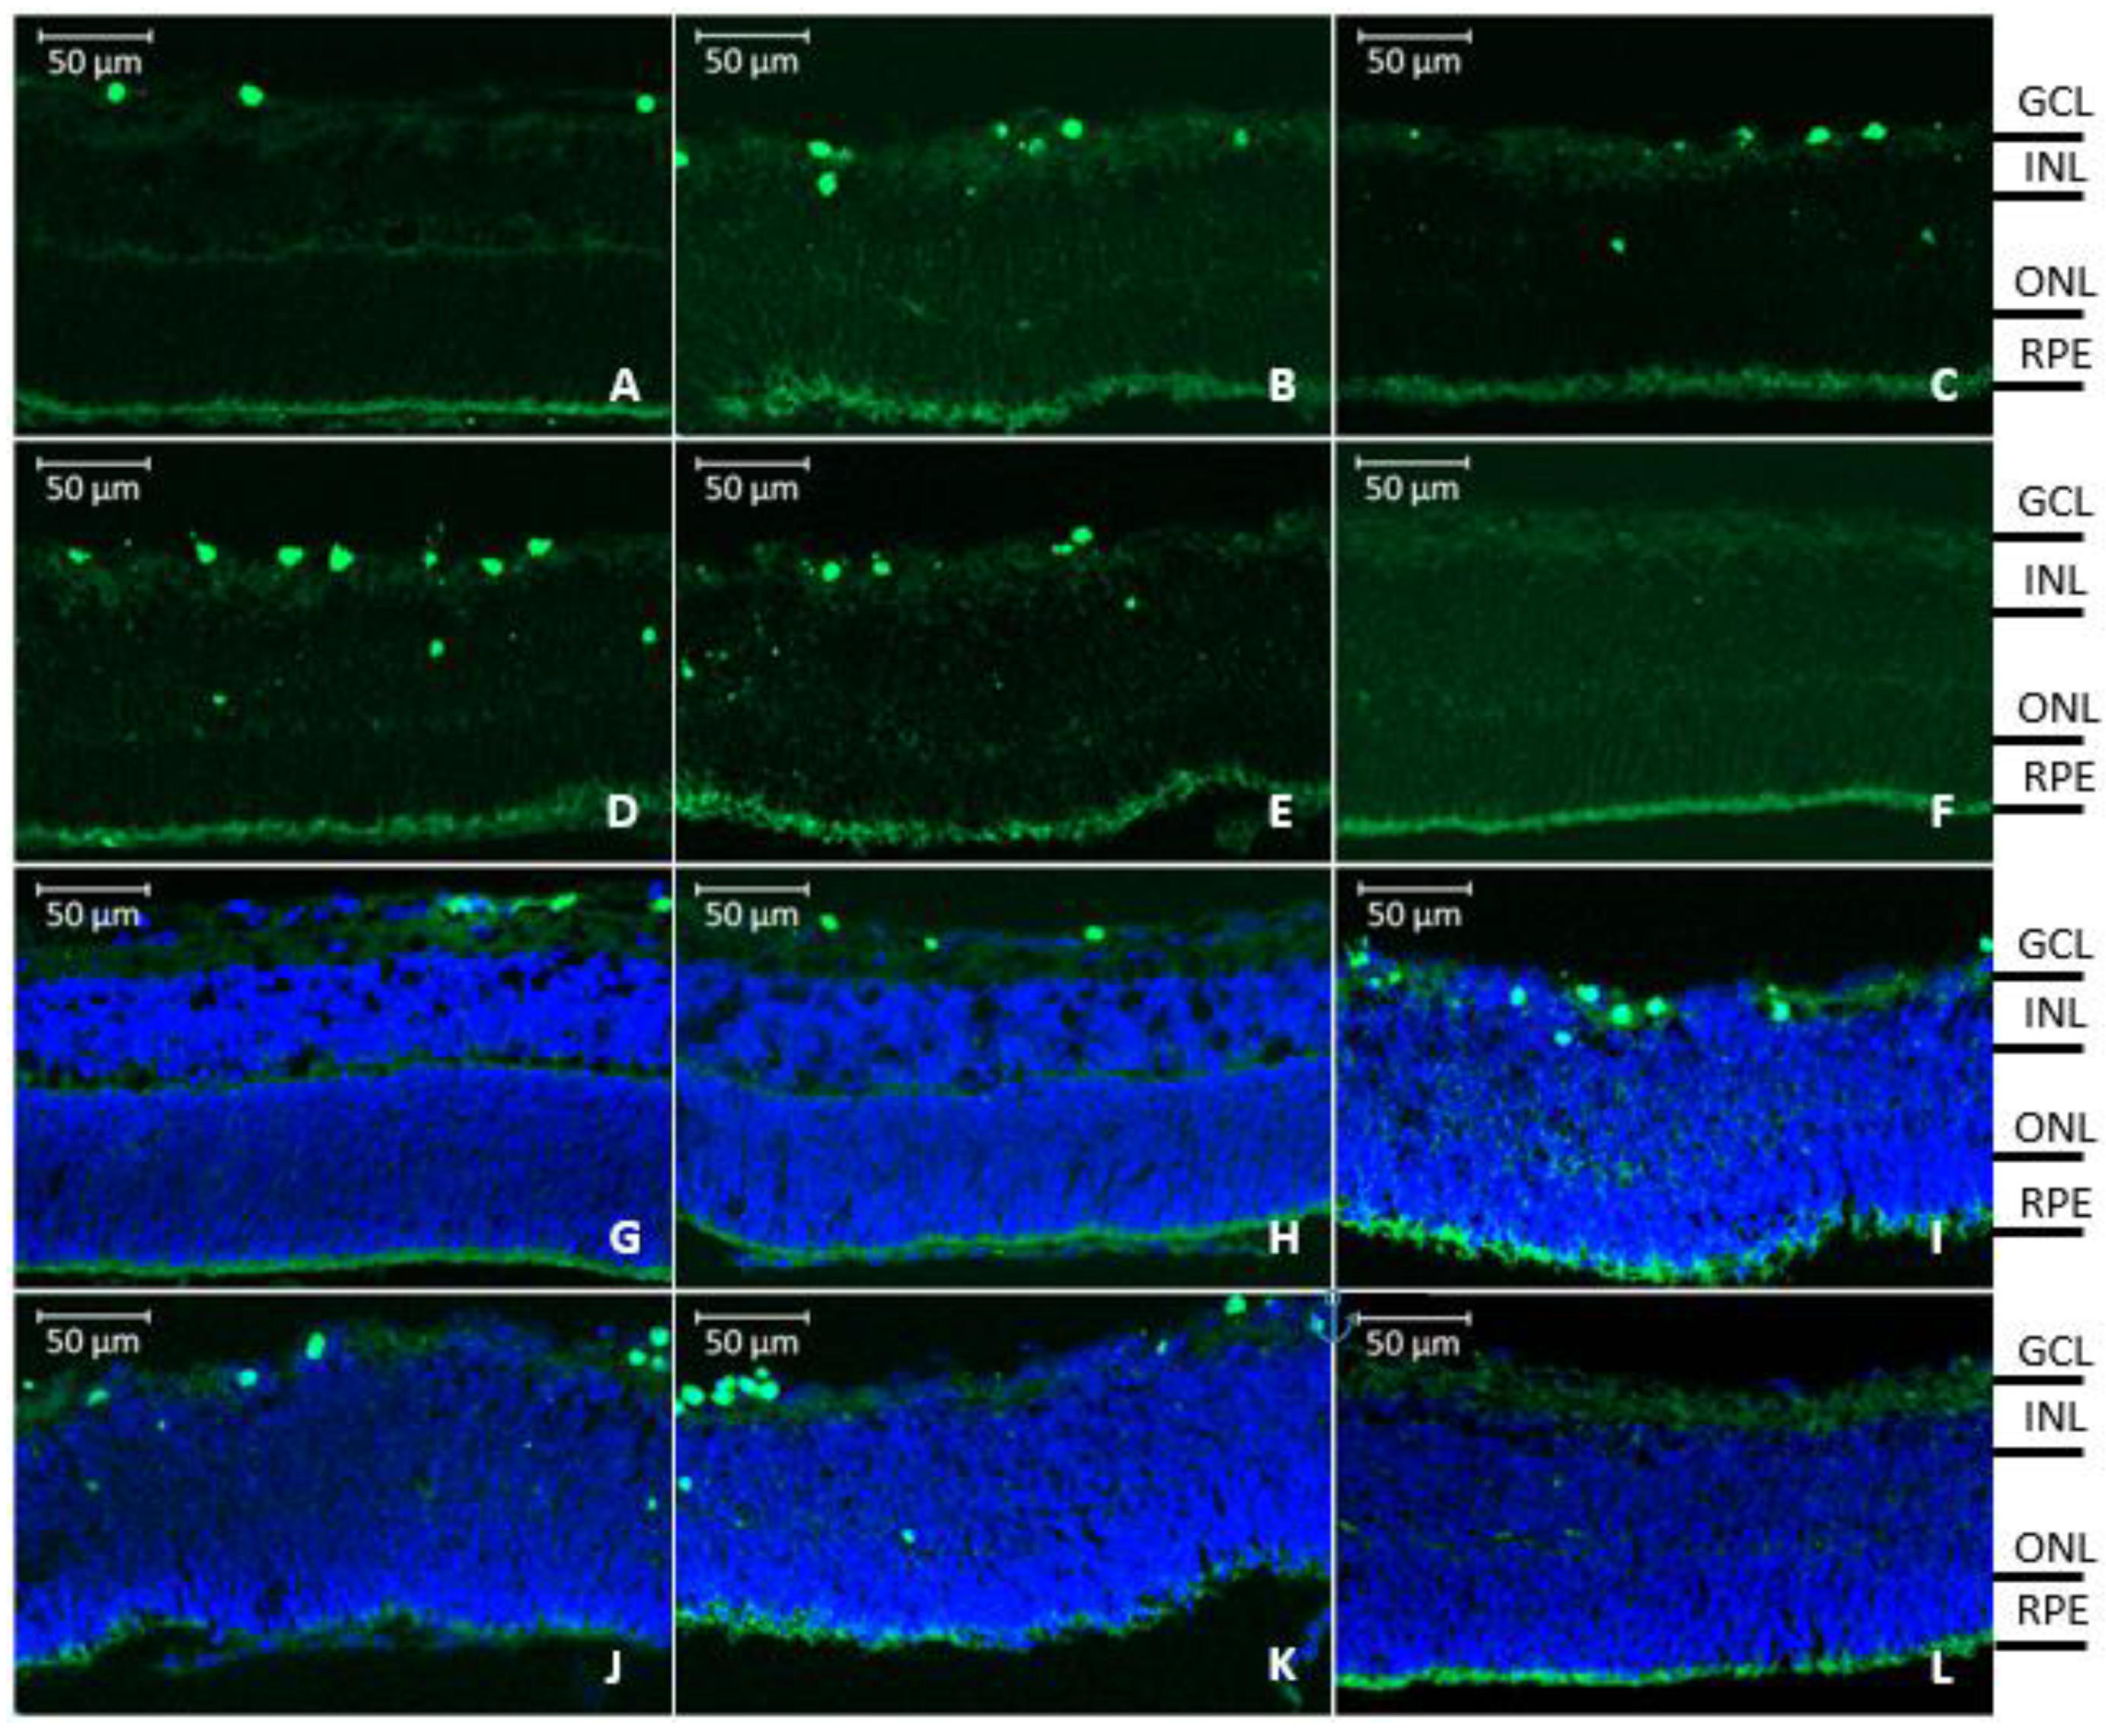

3.5. Retinal Penetration of Labeled rhCNTF

4.3. Retinal Penetration and Effects of rhCNTF